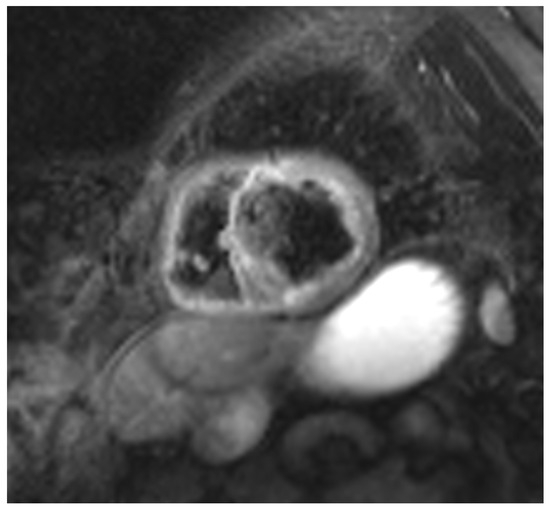

Cardiac sarcoidosis (CS) is a critical and frequently underdiagnosed phenotype of sarcoidosis, characterized by non-caseating granulomatous infiltration of the myocardium. This review synthesizes current knowledge regarding the pathogenesis, diagnosis, and management of CS. The disease manifests with a heterogeneous clinical spectrum ranging from asymptomatic conduction abnormalities to life-threatening ventricular arrhythmias and heart failure. Diagnosis remains challenging due to the patchy distribution of granulomas, which limits the sensitivity of endomyocardial biopsy. Consequently, a multimodal diagnostic approach is essential, integrating advanced imaging modalities such as cardiac magnetic resonance (CMR) with late gadolinium enhancement (LGE) and 18F-fluorodeoxyglucose positron emission tomography (FDG-PET). These tools not only facilitate detection but also enable the differentiation of active inflammation from chronic fibrosis. Histopathological assessment, supported by specific immunophenotyping and electron microscopy, remains the gold standard for confirming diagnosis and excluding mimics like giant cell myocarditis or infectious granulomatous diseases. Management requires a multidisciplinary strategy combining immunosuppressive therapy, primarily corticosteroids and steroid-sparing agents, with guideline-directed cardiac care, including implantable cardioverter-defibrillators for arrhythmia risk stratification. Emerging biomarkers and artificial intelligence-driven imaging analysis promise to further refine risk stratification and therapeutic monitoring, advancing precision medicine in this complex disorder. Full article

Show Figures

Figure 1